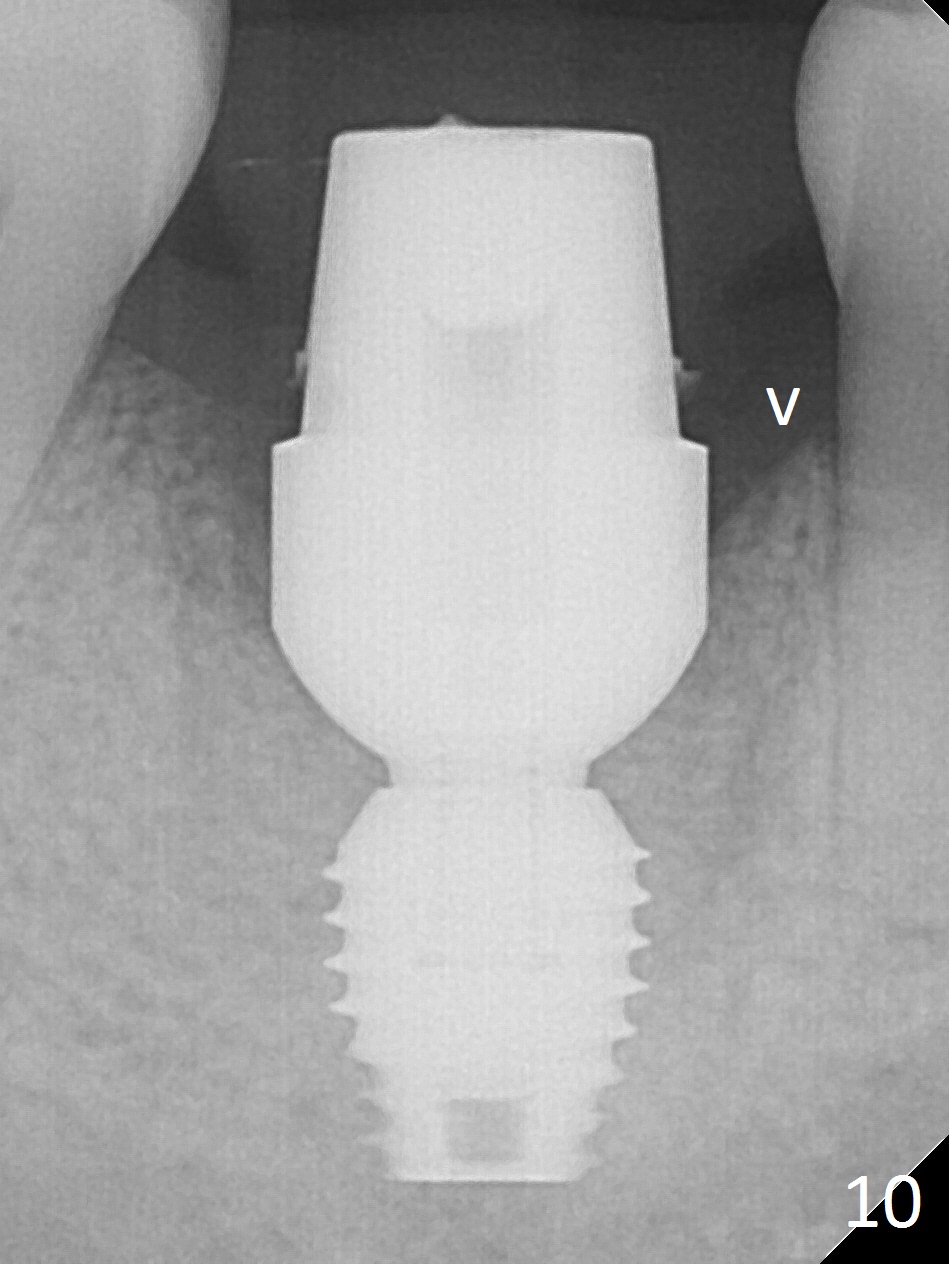

After extraction of the tooth #30 with Class V furcation involvement (Fig.1 (>),2 (L: lingual)), initial osteotomy depth is 8 mm with infiltration anesthesia, but a parallel pin is able to be inserted for 16 mm without pain (Fig.3). There is oozing from the osteotomy. Osteotomy increases in diameter with depth at 8 mm (Fig.4 (3.8 mm drill),5 (5.3 mm tap)). As the Inferior Alveolar Canal (IAC) is indistinct with increased pain during osteotomy, a 5.9x6 mm implant is placed with >50 Ncm following Septocaine infiltration (Fig.6). When bone graft (Fig.7 *) and 7.8x5.5(6) mm abutment (Fig.7,8) are placed, panoramic X-ray is taken (Fig.9). There appears to be a thick layer of spongy bone in the posterior mandible between the red and yellow dashed lines (Fig.5,9). Panoramic X-ray and/or CBCT should be taken if preop PA does not reveal IAC. This patient seems to be a bruxer. There are mandibular tori. Bone loss (furcation involvement) is not proportional to his oral hygiene status. Functional loading (progressive) should be delayed due to bruxism and the short implant.

The bone (Fig.10 arrowhead) and soft tissue (Fig.11 *) heal 2 months postop. Gingivectomy is done with Diode prior to impression (Fig.12). The provisional is relined to keep the margin (Fig.13, 2 weeks later) and a permanent crown tries in (Fig.14).